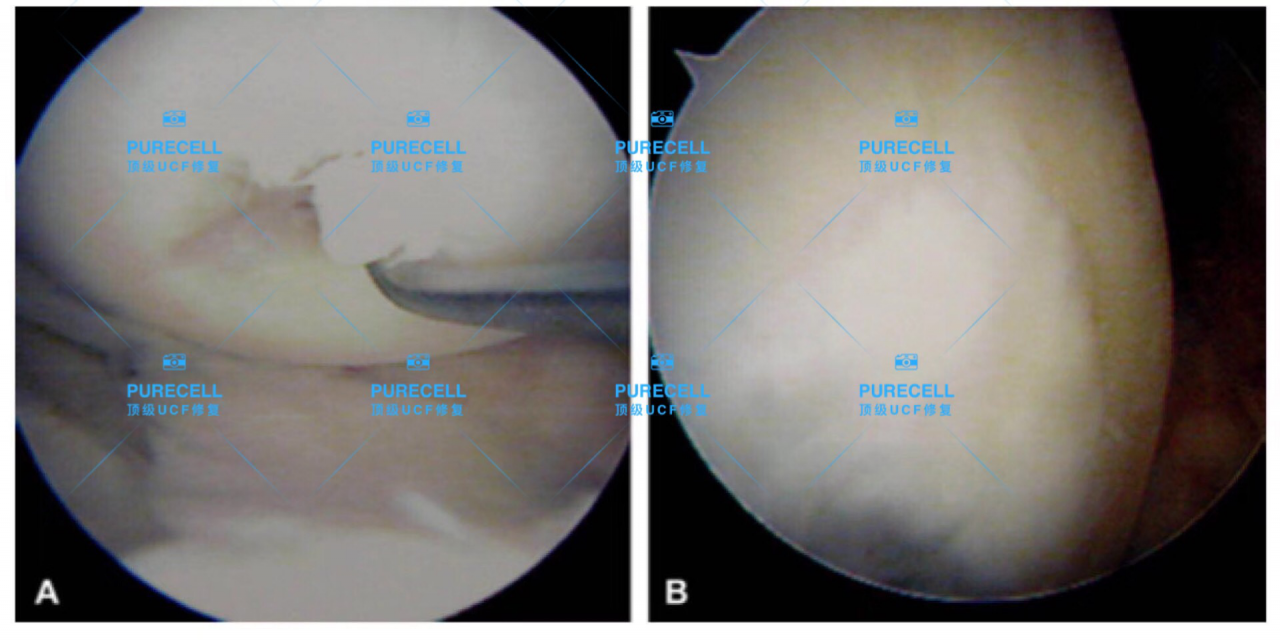

PURECELL首席科學家以及運動醫療專家已經驗證了UCF對膝關節修復的有效性,下圖是UCF軟骨及半月板修復前後影像對比。

PURECELL金牌資質醫生Dr. Ian Chinse說,UCF膝關節修復的主要原理是通過UCF成分,改善膝關節內環境,有效激活幹細胞靶向修復膝關節組織,修復韌帶損傷、半月板損傷,修復軟骨及髕骨等組織,能有效較少軟骨受損、骨刺等所帶來的疼痛,並且有效避免了軟骨、半月板等膝關節組織的持續磨損和惡化,從根源上改善膝關節疼痛等問題給生活帶來的困擾。

UCF膝關節修復一經面世,已經為成百上千的運動損傷及老年退行性病變的客人帶來意想不到的修復效果,滿意度回饋達99%以上。不開刀,不手術,微創、無痛、便利,不會造成二次損傷,是迄今為止,最理想、最革新的膝關節修復科技。